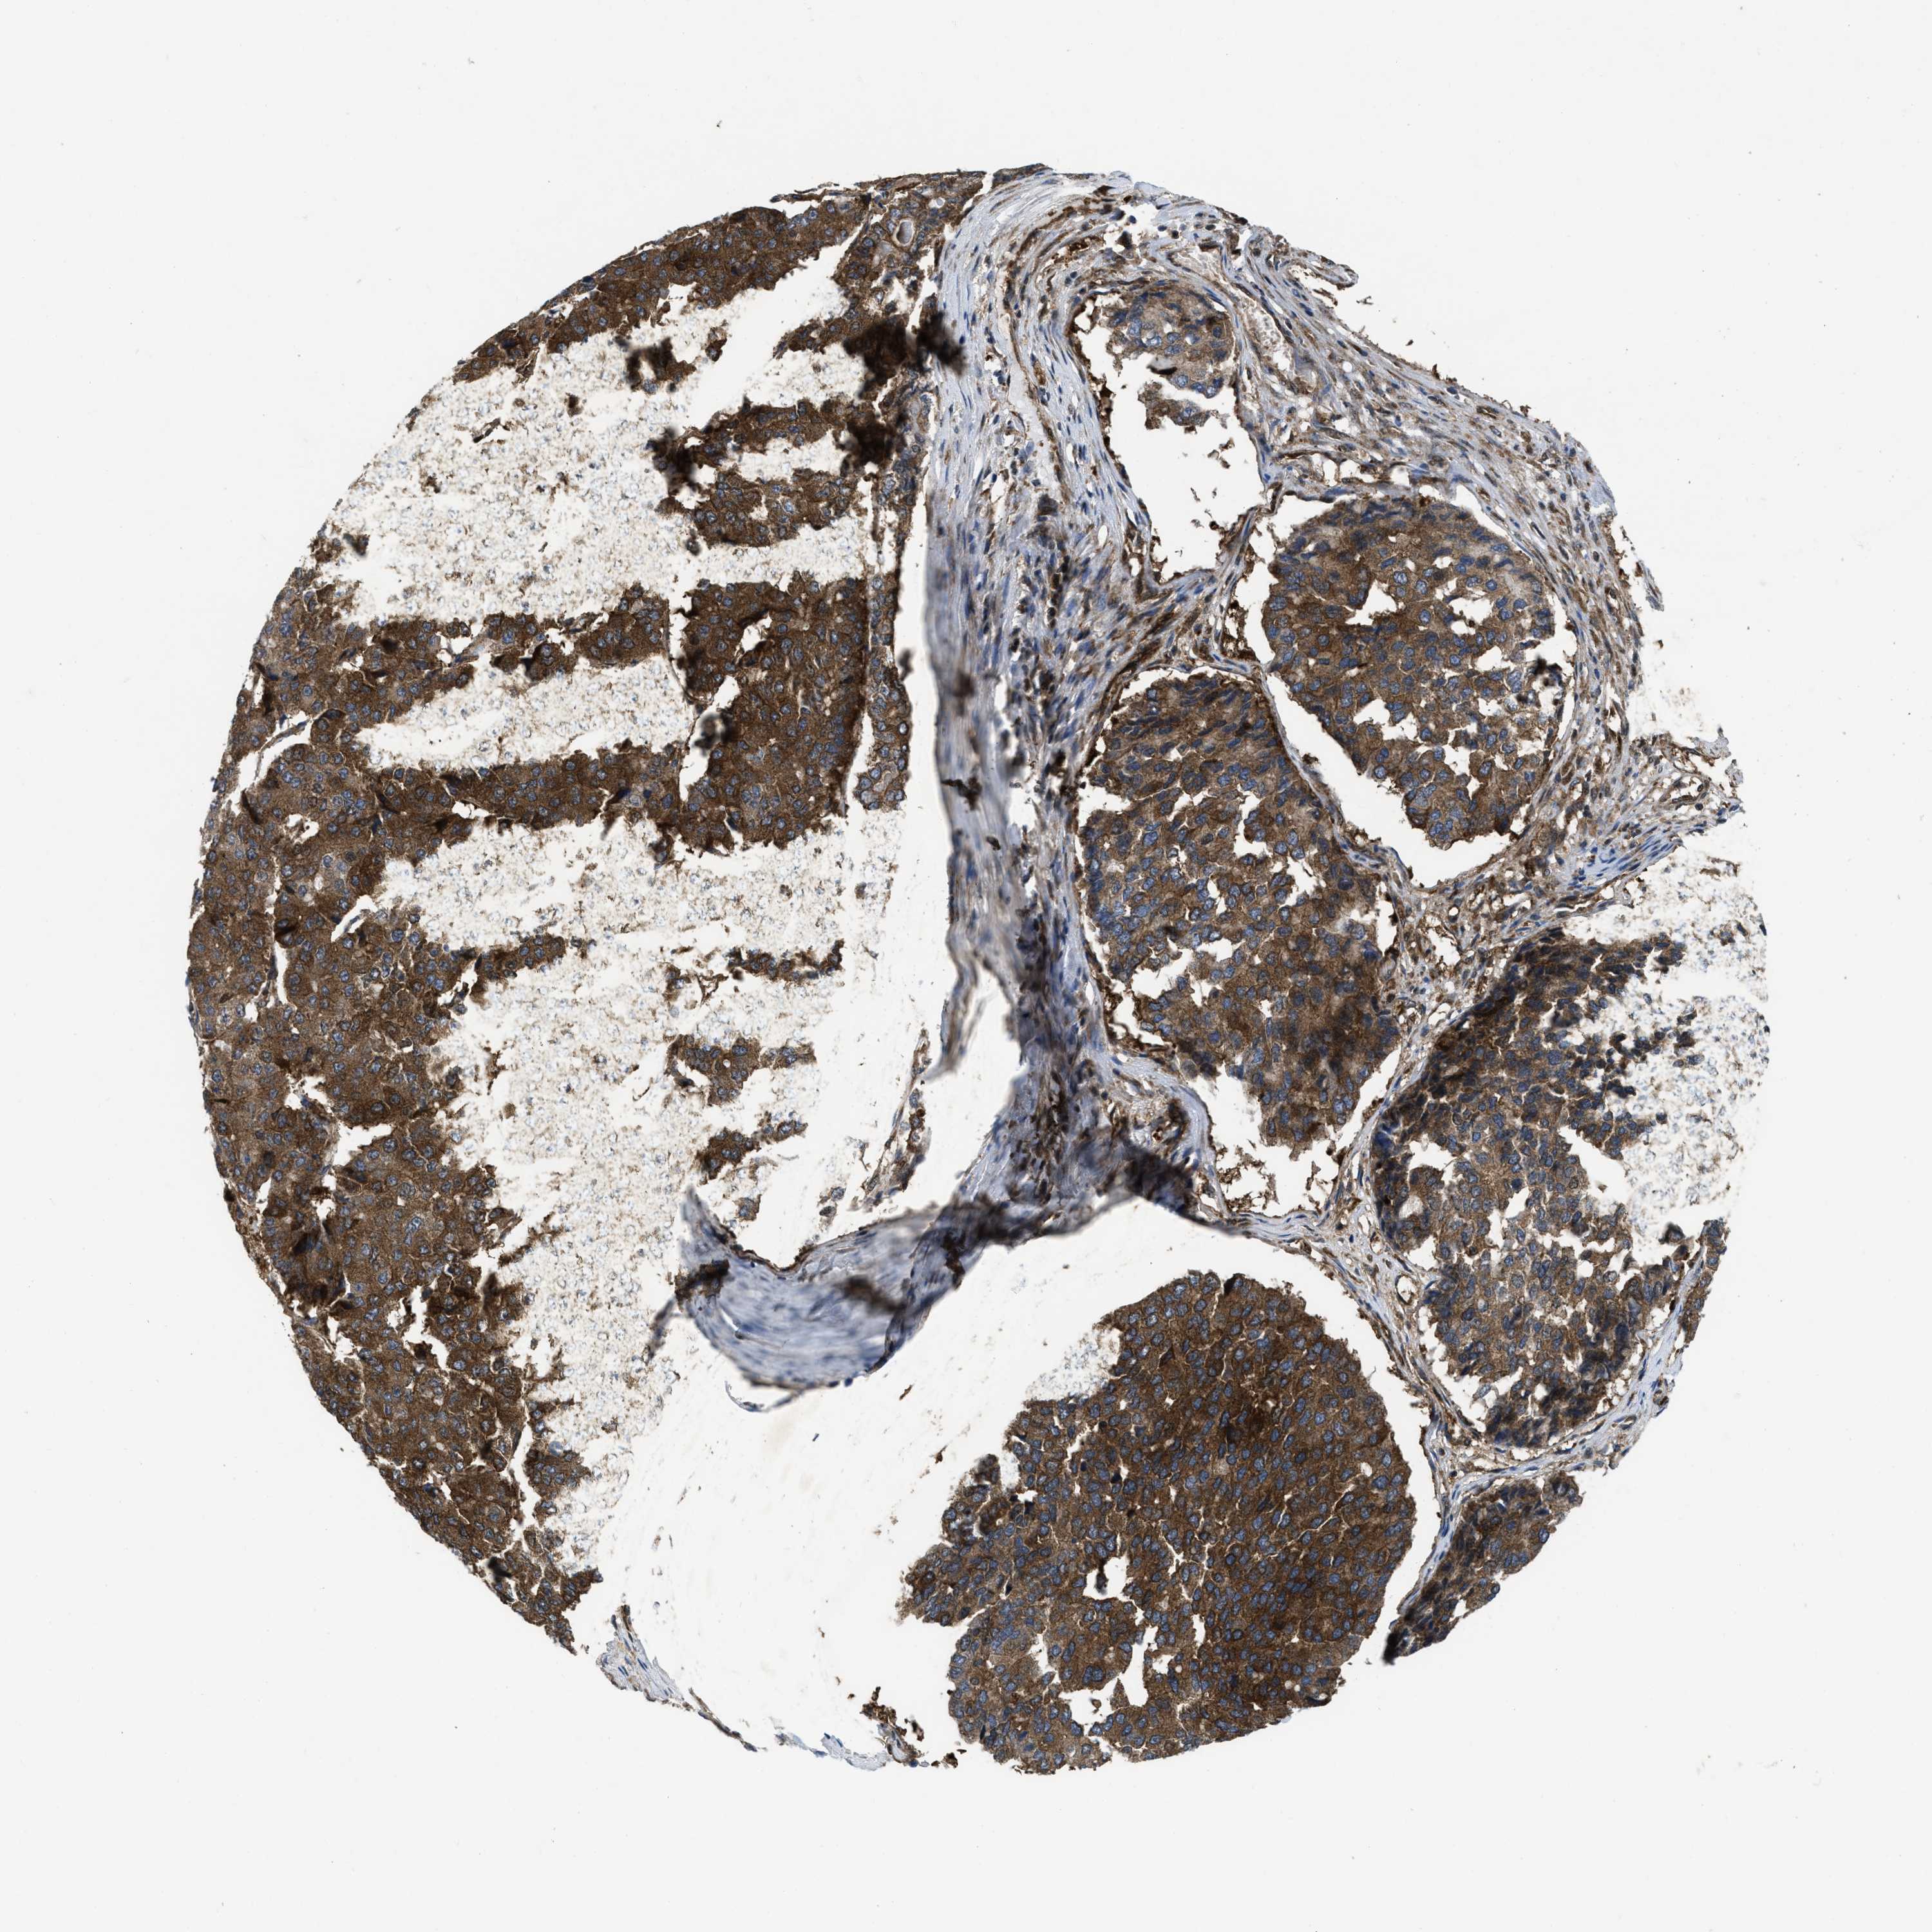

PANCREATIC CANCER - Protein expressioni

A mouse-over function shows sample information and annotation data. Click on an image to view it in a full screen mode. Samples can be filtered based on level of antibody staining by selecting one or several of the following categories: high, medium, low and not detected. The assay and annotation is described here.

Note that samples used for immunohistochemistry by the Human Protein Atlas do not correspond to samples in the TCGA dataset.

Antibody stainingi

Antibody staining in the annotated cell types in the current human tissue is reported as not detected, low, medium, or high, based on conventional immunohistochemistry profiling in selected tissues. This score is based on the combination of the staining intensity and fraction of stained cells.

Each image is clickable and will lead to virtual microscopy that enables deeper exploration of all samples and also displays staining intensity scores, fraction scores and subcellular localization as well as patient and tissue information for each sample.

Antibody HPA043236

Antibody CAB018600

Staining

High

Medium

Low

Not detected

Intensity

Strong

Moderate

Weak

Negative

Quantity

>75%

75%-25%

<25%

None

Location

Nuclear

Cytoplasmic/membranous

Cytoplasmic/membranous,nuclear

Adenocarcinoma, NOS